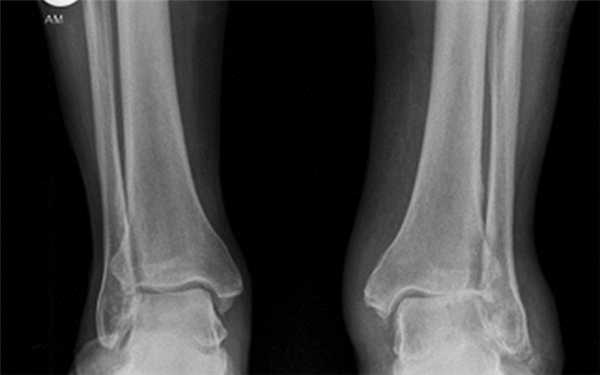

Методика рентгенологической диагностики повреждений голеностопного сустава (рис. 14.5, 14.6)

Обязательным является выполнение рентгенограмм в прямой и боковой проекциях при тщательной центрацией рентгеновского пучка точно на область голеностопного сустава. Для выполнения прямой и боковой рентгенограмм голень необходимо ротировать кнутри на 20°. В этом положении чрезлодыжечная ось параллельна рентгеновской пластинке (рис. 14.16а,с). Косой перелом диафиза малоберцовой кости, который часто ошибочно принимают за изолированное повреждение, почти всегда представляет собой перелом типа С. В подобных случаях необходимо внимательное рентгенологическое обследование голеностопного сустава для выявления сопутствующих повреждений в вилке сустава. Если имеется подозрение на повреждение переднего большеберцового бугорка (бугорка Тилло-Шапута), то выполняют дополнительное рентгенологическое исследование с наружной ротацией голени на 45°. Если имеются клинические признаки серьезного повреждения голеностопного сустава, а рентгенограмма выглядит нормальной, то следует думать о травме типа С с проксимальным или даже субкапитальным переломом малоберцовой кости. Поэтому рентгенограммы должны захватывать как голеностопный сустав, так и малоберцовую кость по всей длине.

Для определения повреждений боковых связочных структур выполняют прямую и боковую с нагрузкой рентгенограммы (рис. 14.6Ь). Изолированные разрывы Lig. fibulotalare anterius не всегда приводят к варусному заклиниванию таранной кости на прямой рентгенограмме с нагрузкой. Однако это приведет к передней нестабильности таранной кости, что можно определить на боковом снимке с нагрузкой(рис. 14.6с). Лишь при дополнительном разрыве Lig. calcaneofibulare будет заметно варусное смещение таранной кости. Рентгенограммы с нагрузкой поврежденного голеностопного сустава будут достоверными лишь в том случае, если их выполняют под местной, регионарной или общей анастезией и сравнивают со снимками голеностопного сустава с неповрежденной стороны.